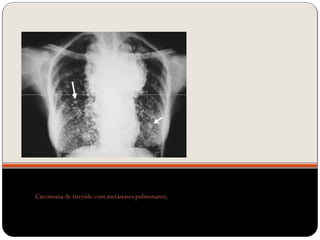

Carcinoma de tireóide com metástases pulmonares;

Nódulos  O nódulopulmonar é uma lesão arredondada ou ovalada, de limites parcialmente precisos, com menos de 3 cm de diâmetro.

Nódulo pulmonar solitário– Não se avalia por TCAR!!!! (TCAR é para doenças difusas)

Carcinoma de tireóidecom metástases pulmonares;